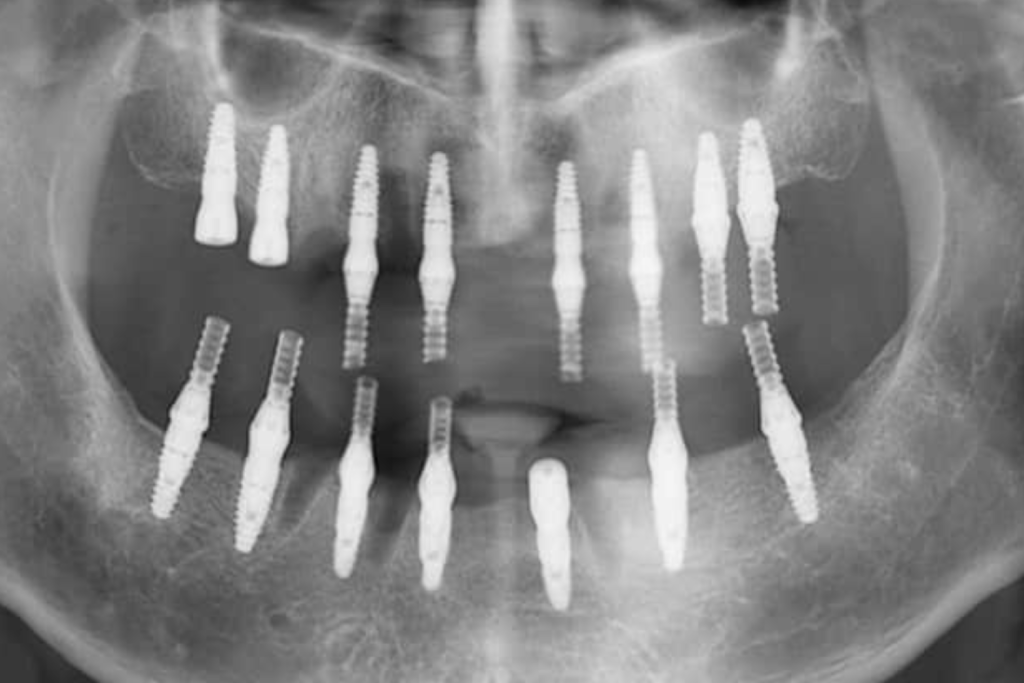

術後X光